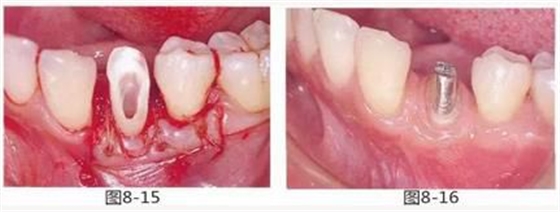

圖8-15 用齦瓣覆蓋結(jié)締組織瓣。

圖8-16 取模時(shí)修復(fù)體的狀態(tài)。牙齦溝約1mm,附著齦增加。